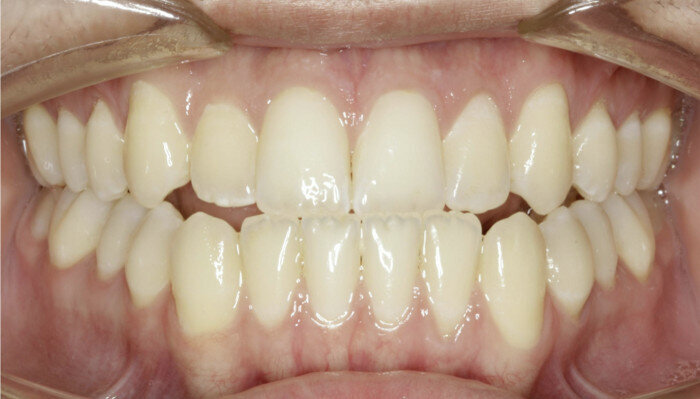

In some cases, intrusion may occur asymmetrically (one side faster than another, or the anterior faster than the posterior). For these occurrences, when one area has been completed with intrusion, the TAD is tied to the wire and intrusion continues in the others until all intrusion has been completed. A gingivectomy and hard-tissue contouring are completed (Figs. 27–29, end of treatment).

Fig. 7

Fig. 8

Fig. 9

Fig. 10

Fig. 11

Fig. 12